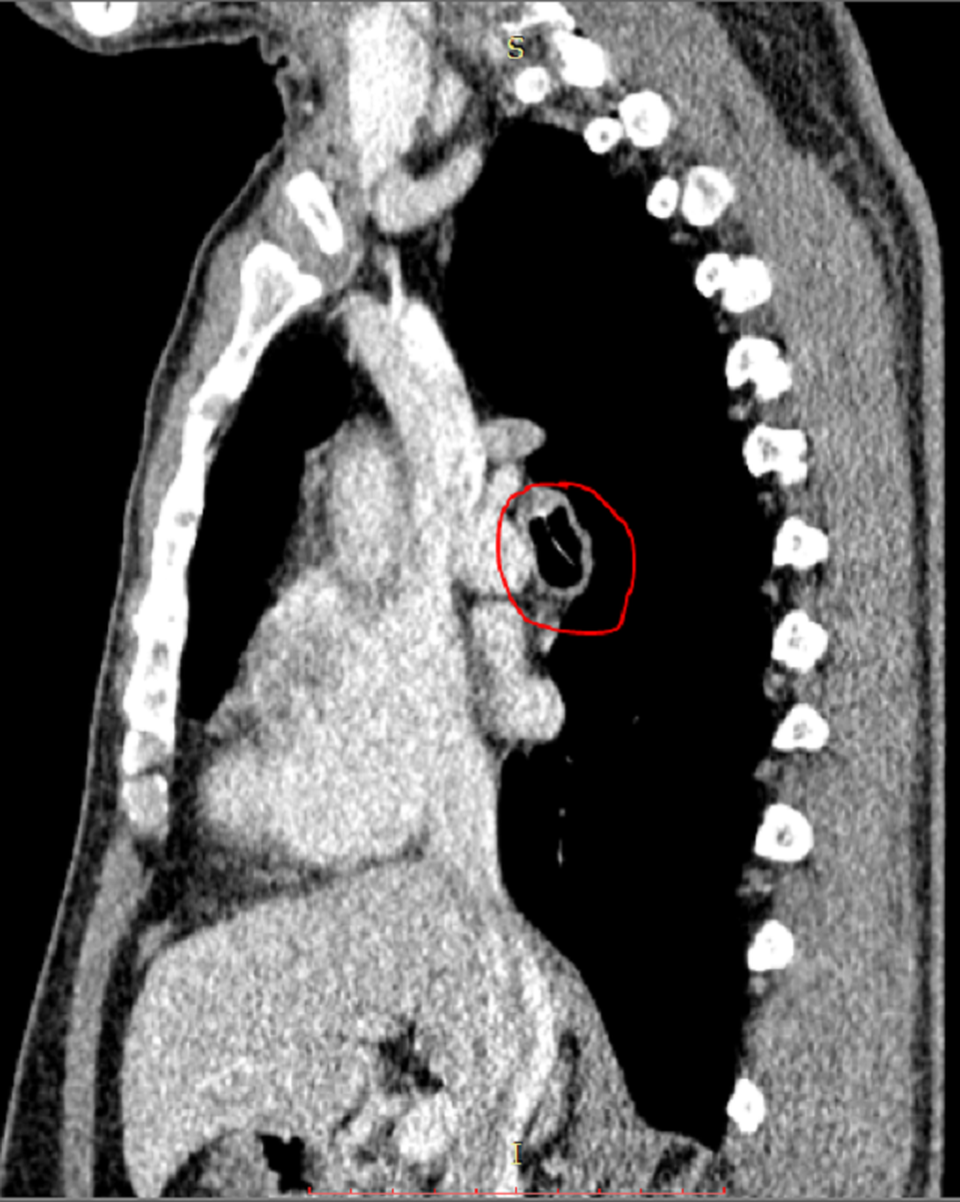

Hình quản CT cho thấy dị vật nằm ở vị trí sát động mạch rất nguy hiểm

Tại khoa Nội tổng quát, bệnh nhân được bác sĩ chỉ định chụp CT. Kết quả chẩn đoán hình ảnh ghi nhận vùng phế quản phải, nằm sát động mạch phổi có dị vật lạ không rõ bản chất, kèm viêm xung huyết quanh dị vật. Sau hội chẩn, bác sĩ nhận định đây là trường hợp bị dị vật “bỏ quên” nên chỉ định nội soi gắp ra ngoài.

Tuy nhiên, dị vật nằm ở vị trí rất nguy hiểm khiến người bệnh đối mặt với nguy cơ tổn thương động mạch phổi dẫn đến xuất huyết, nguy hiểm đến tính mạng. Sau khi chuẩn bị, ê kíp các bác sĩ đã nhanh chóng nội soi qua đường mũi gắp thành công mảnh xương cá nằm trong phế quản.